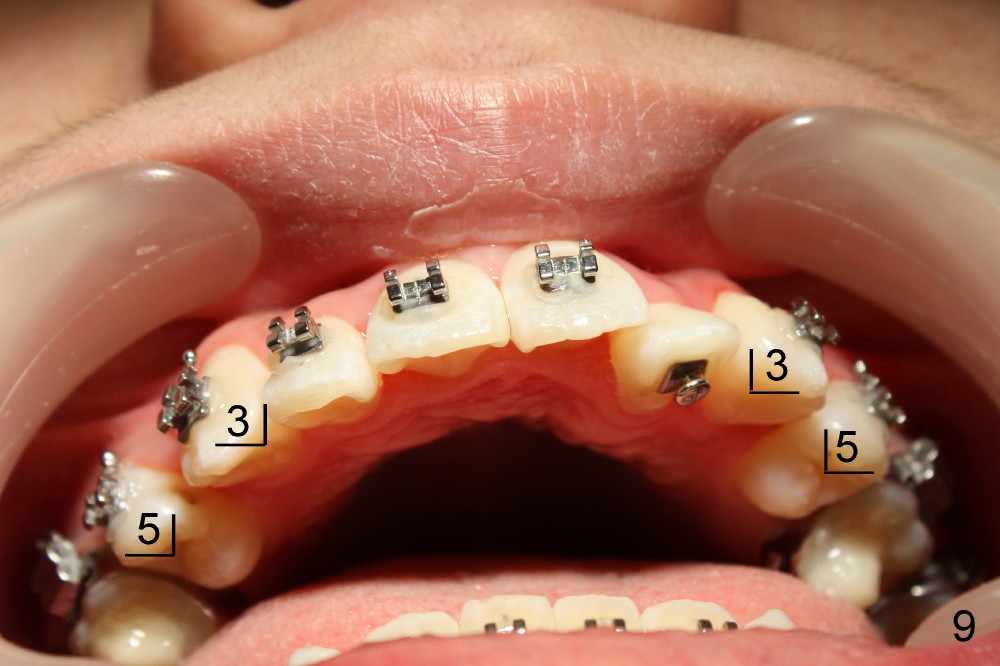

Five weeks later, .018 ss wires are installed with open coil spring between UL 1 and 3 and power chain between UL 3 and 7 (Fig.4). Three months post-bracketing, space is being created for UL 2 (Fig.5). Four months post-bracketing, a lingual button is placed on UL2 with power chain x7 (Fig.6: sling shot); Pletcher's spring between UL 3 and 7 (^).

Five months into treatment, cross bite of UL2 is corrected (Fig.9); there is no space between UL3 and 5, but there is space between UR 3 and 5.